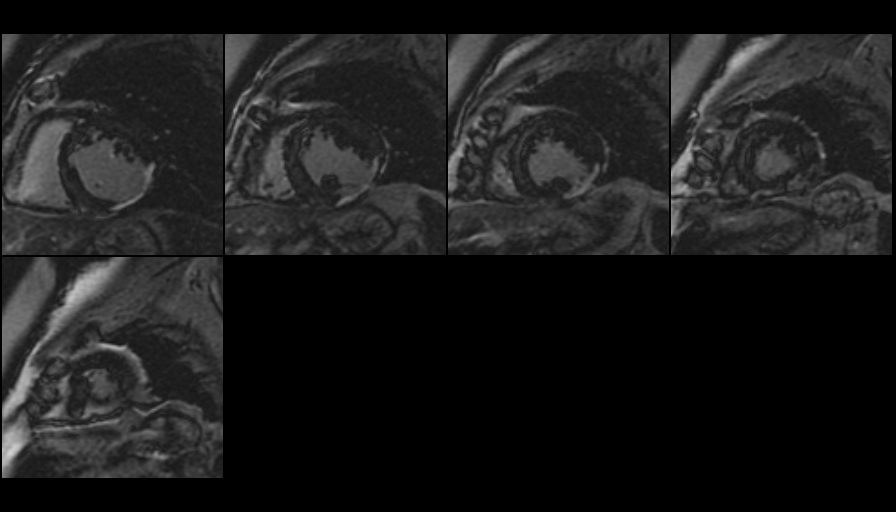

The Heart Station provides high-quality noninvasive diagnostic testing for our patients including transthoracic echocardiography, transesophageal echocardiography and exercise and pharmacologic stress testing. The lab is equipped with state-of-the art ultrasound machines including Philips Epiq and IE33s systems. The lab performs over 6000 TTEs and TEEs per year and procedures include 3D echocardiography, intraoperative TEE, and TEE guidance for structural heart disease.

The Heart Station is accredited by the International Commission for the Accreditation of Echocardiography Laboratories (ICAEL), indicating a high level of quality care and standards for its patients.

As the Heart Station fellow, you will:

- Be exposed to a diverse range of cardiac pathology, often newly diagnosed

- As a first year fellow you will acquire and interpret TTEs

- As a senior fellow you will acquire and interpret both TTEs and TEEs